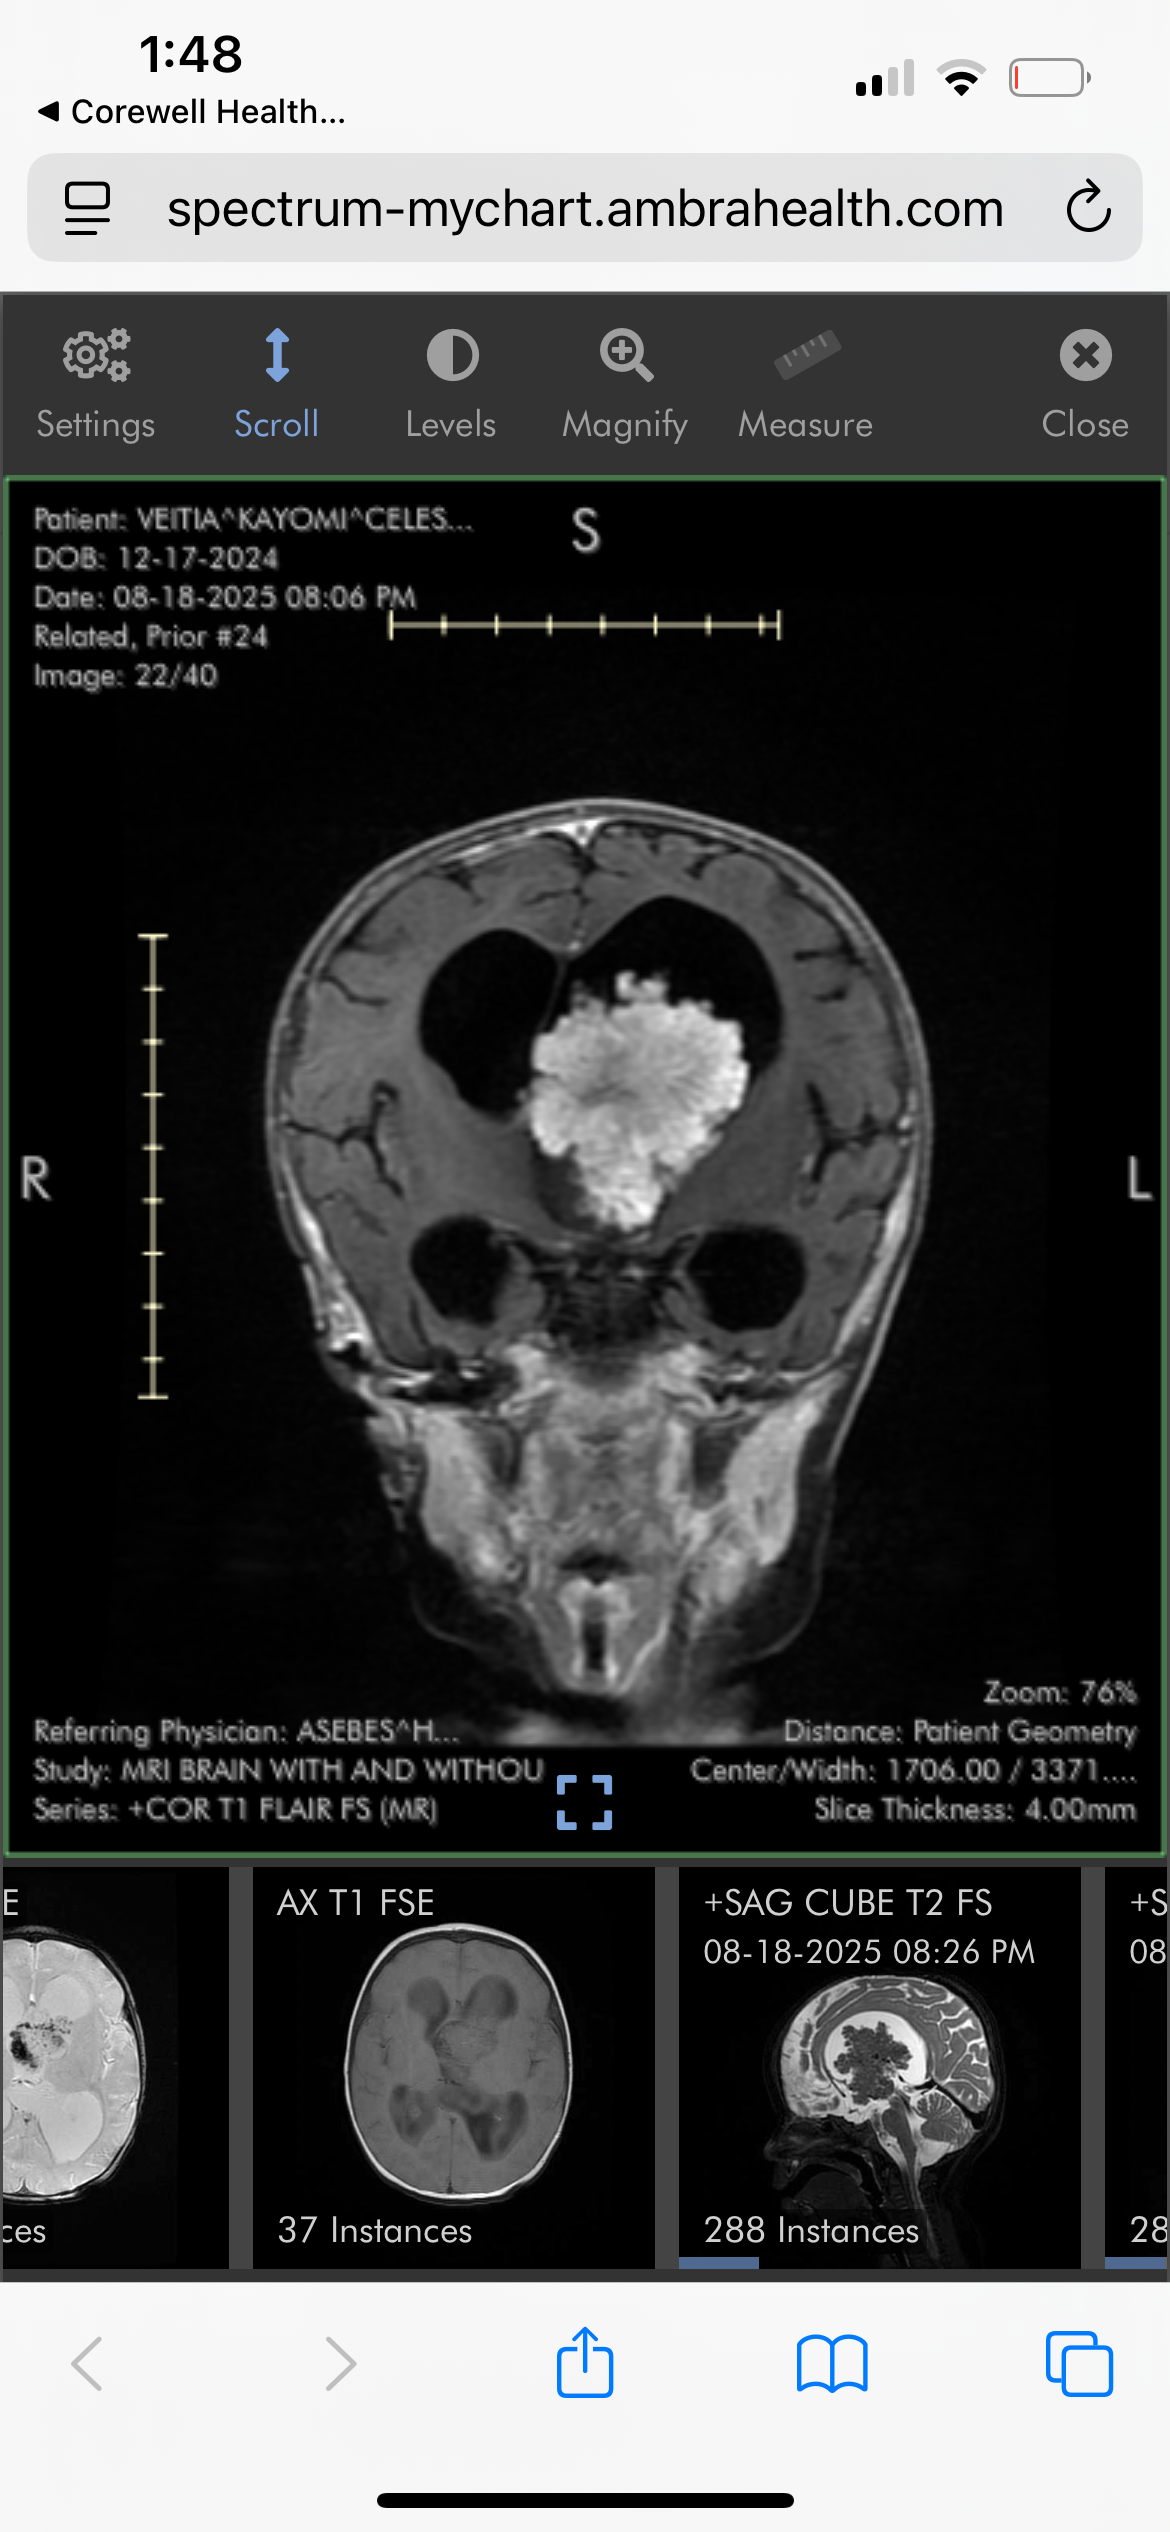

My name is Taylor, I am 20 years old and the mother of 10-month-old Kay’Omi Celeste. On August 18th, 2025, my then 8-month-old, Kay’Omi, was unexpectedly diagnosed with a large brain tumor.

This has changed both of our lives drastically overnight. Kay’Omi has had multiple surgeries within these two months. She has also had multiple doctor’s appointments and long hospital stays. We are currently unsure if the tumor is cancerous or not, or what exactly it is, but she is getting chemotherapy just in case it is and to shrink it before they are able to take it out. I’m still processing the fact that my baby is going through this so young.